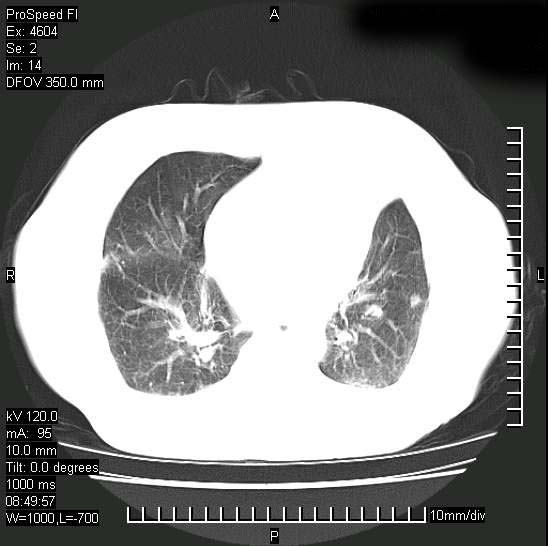

短短几天内,病变范围明显增多扩大,以左侧明显,而且双侧出现胸水,还是考虑感染.

短短几天内,病变范围明显增多扩大,以左侧明显,而且双侧出现胸水,我更多考虑左侧中心性肺癌并并阻塞性不张及肺炎,炎症变化也太快了!

无论是肿瘤还是炎症4天的时间都发展够快的,并且还在治疗中,如果说是左肺癌那么右肺的病变不好解释,本人更加倾向于炎症,左肺舌叶支气管被痰栓或血凝块堵塞,造成阻塞性肺炎。

1)两肺结核并感染。2)不排除左肺上叶中央型肺癌并阻塞性肺炎、肺不张可能;建议行纤支镜检查。3)右肺门及纵隔淋巴结肿大。4)双侧胸腔积液。